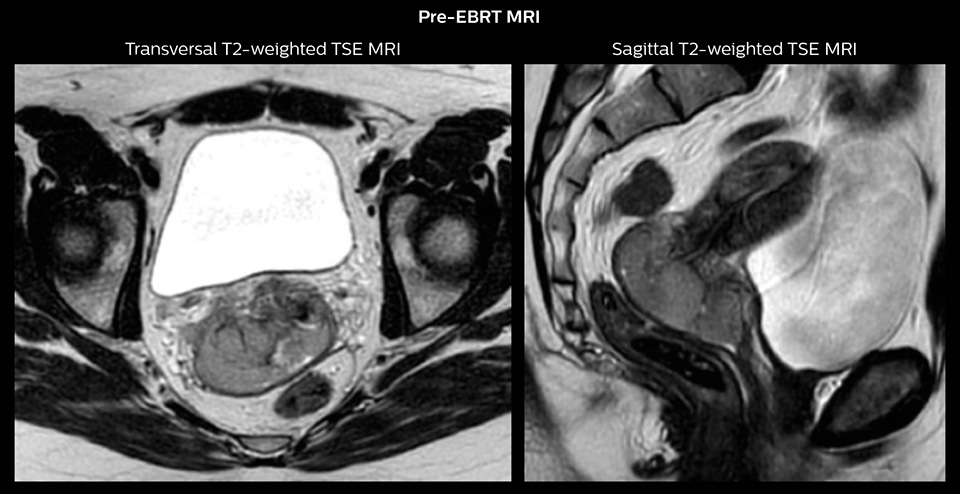

Case study: MR-guided brachytherapy in patient with cervix cancer

Patient history

Stage IIB cervix cancer patient with a primary tumor with width of 6.0 cm and proximal/distal infiltration of left/right parametria at diagnosis. The patient had one PET-positive external iliac lymph node.

The patient was treated with external beam radiotherapy (EBRT) and concomitant chemotherapy. EBRT was delivered as IMRT with daily IGRT and a total dose of 45 Gy in 25 fractions to the pelvis and 55/25 fractions to the PET-positive lymph node. There was good tumor response during therapy and towards the end of EBRT the primary tumor had regressed to 3.8 cm width and proximal parametrial infiltration.

Brachytherapy

Two pulsed dose rate (PDR) brachytherapy fractions were delivered after end of EBRT in weeks 6 and 7.

One week prior to the first brachytherapy fraction, pre-planning was performed. Pre-planning involved insertion of intracavitary tandem-ring applicator and MR imaging with applicator in place.

An MRI-based pre-plan was carried out to determine the number, position and length of needles to be implanted through the ring applicator. Brachytherapy was delivered with the tandem ring applicator combined with 6 interstitial plastic needles.

Pre-EBRT MRI Sagittal